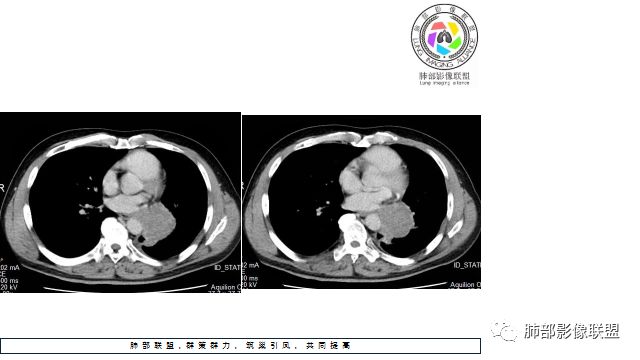

1.左下肺门区巨大肿块,支气管显示不清,轻度阻塞性炎症,没有明显肺不张,提示管腔受压狭窄可能性大于堵塞,这较少见于鳞癌。

3.病灶内密度均匀,轻到中度均匀强化,大病灶未见明显液化坏死区及空洞,不符合鳞癌而符合小细胞肺癌特点。

4.病灶内有肺动脉走形,血管局部受压,未见破坏,病灶乏血供,呈血管包埋或血管造影征;侵袭性力强及破坏力弱、血管漂浮都符合SCLC,所以鳞癌的可能性也不大。

5.左肺门块影或淋巴结肿大,竭力挤兑肺门血管结构,呈冰冻肺门;有时候SCLC可以单独呈现冰冻肺门,而没有没有冰冻纵隔。